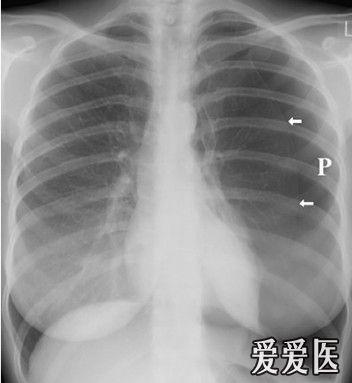

气胸影像图片,气胸胸片典型图片

气胸胸片典型图片